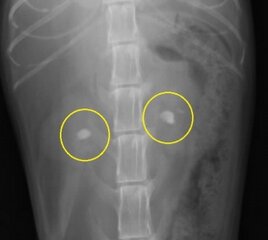

下の写真は両側の腎盂内に比較的大きな腎結石が発見された猫の腹部レントゲン写真です。上写真が縦方向下が横方向のものです。

下のレントゲン像の黄色の縁で囲んだ目立たない結石は画像でこそ目立ちませんが、急性の尿管閉塞を生じている尿管結石です。尿管閉塞というのはお腹の中で腎臓から膀胱をつなぐ細い尿管で生じます。尿路閉塞として一般的な膀胱結石による尿道閉塞とその仕組みは同じです。